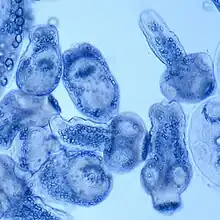

From the embryo released from an egg develops a hydatid cyst, which grows to about 5–10 cm within the first year and is able to survive within organs for years.[25] Cysts sometimes grow to be so large that by the end of several years or even decades, they can contain several liters of fluid. Once a cyst has reached a diameter of 1 cm, its wall differentiates into a thick outer, non-cellular membrane, which covers the thin germinal epithelium. From this epithelium, cells begin to grow within the cyst. These cells then become vacuolated, and are known as brood capsules, which are the parts of the parasite from which protoscolices bud. Often, daughter cysts also form within cysts.[24]

Echinococcus adult worms develop from protoscolices and are typically 6 mm or less in length and have a scolex, neck and typically three proglottids, one of which is immature, another of which is mature and the third of which is gravid (or containing eggs).[24] The scolex of the adult worm contains four suckers and a rostellum that has about 25–50 hooks.[26]

Polycystic

Similar to the diagnosis of alveolar echinococcosis and cystic echinococcosis, the diagnosis of polycystic echinococcosis uses imaging techniques, in particular ultrasonography and CT scans, to detect polycystic structures within the person's body. However, imaging is not the preferred method of diagnosis since the method that is currently considered the standard is the isolation of protoscoleces during surgery or after the person's death and the identification of definitive features of E. oligarthrus and E. vogeli in these isolated protoscoleces. This is the main way that PE is diagnosed, but some current studies show that PCR may identify E. oligarthrus and E. vogeli in people's tissues.[33] The only drawback of using PCR to diagnose polycystic echinococcosis is that there aren't many genetic sequences that can be used for PCR that are specific only E. oligarthrus or E. vogeli.[19]